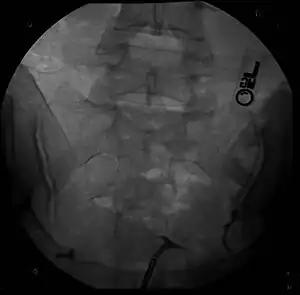

- The two Müllerian ducts have fused, but the partition between them is still present, splitting the system into two parts. With a complete septum the vagina, cervix and the uterus can be partitioned. Usually the septum affects only the cranial part of the uterus. A uterine septum is the most common uterine malformation and a cause for miscarriages. It is diagnosed by medical image techniques, i.e. ultrasound or an MRI. MRI is considered the preferred modality due to its multiplanar capabilities as well as its ability to evaluate the uterine contour, junctional zone, and other pelvic anatomy. A hysterosalpingogram is not considered as useful due to the inability of the technique to evaluate the exterior contour of the uterus and distinguish between a bicornuate and septate uterus. This condition can be complete or partial

Besides a physical examination, the physician will need imaging techniques to determine the character of the malformation: gynecologic ultrasonography, pelvic MRI, or hysterosalpingography. A hysterosalpingogram is not considered as useful due to the inability of the technique to evaluate the exterior contour of the uterus and distinguish between a bicornuate and septate uterus. In addition, laparoscopy and/or hysteroscopy may be indicated. In some patients the vaginal development may be affected.